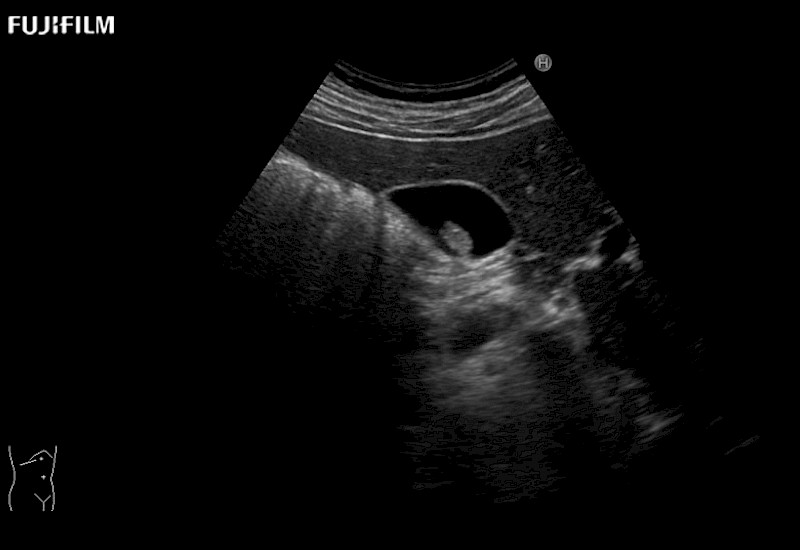

Our dedication to Laparoscopic Surgery allows us to offer superior image quality, outstanding system reliability and intuitive use of cutting edge technology.

The ARIETTA 750 incorporates all of the proven technologies and functions that medical professionals have come to expect from Fujifilm Healthcare.

ARIETTA 750 is the definitive diagnostic ultrasound solution for any clinical setting - Private Office, Imaging Center, or Hospital. The ARIETTA platform provides the ultimate in clinical performance with its state-of-the-art features and large user-friendly display.

The ARIETTA 650 DI combines trusted Fujifilm Healthcare technologies and features tailored for surgical oncology.

Designed to meet the demands of surgeons, the ARIETTA 650 DI offers precise guidance. Its advanced capabilities and large, intuitive display offer accurate and efficient care in operating rooms and specialized surgical settings.